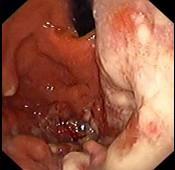

问题 患者,女,19岁,反复发热、上腹痛、消瘦1月,查体:上腹部饱满,余无阳性体征。电子胃镜图片如下,诊断为 ( )

选项 A.胃癌 B.胃淋巴瘤 C.胃溃疡 D.胃溃疡并真菌感染 E.胃多发性息肉

答案 B